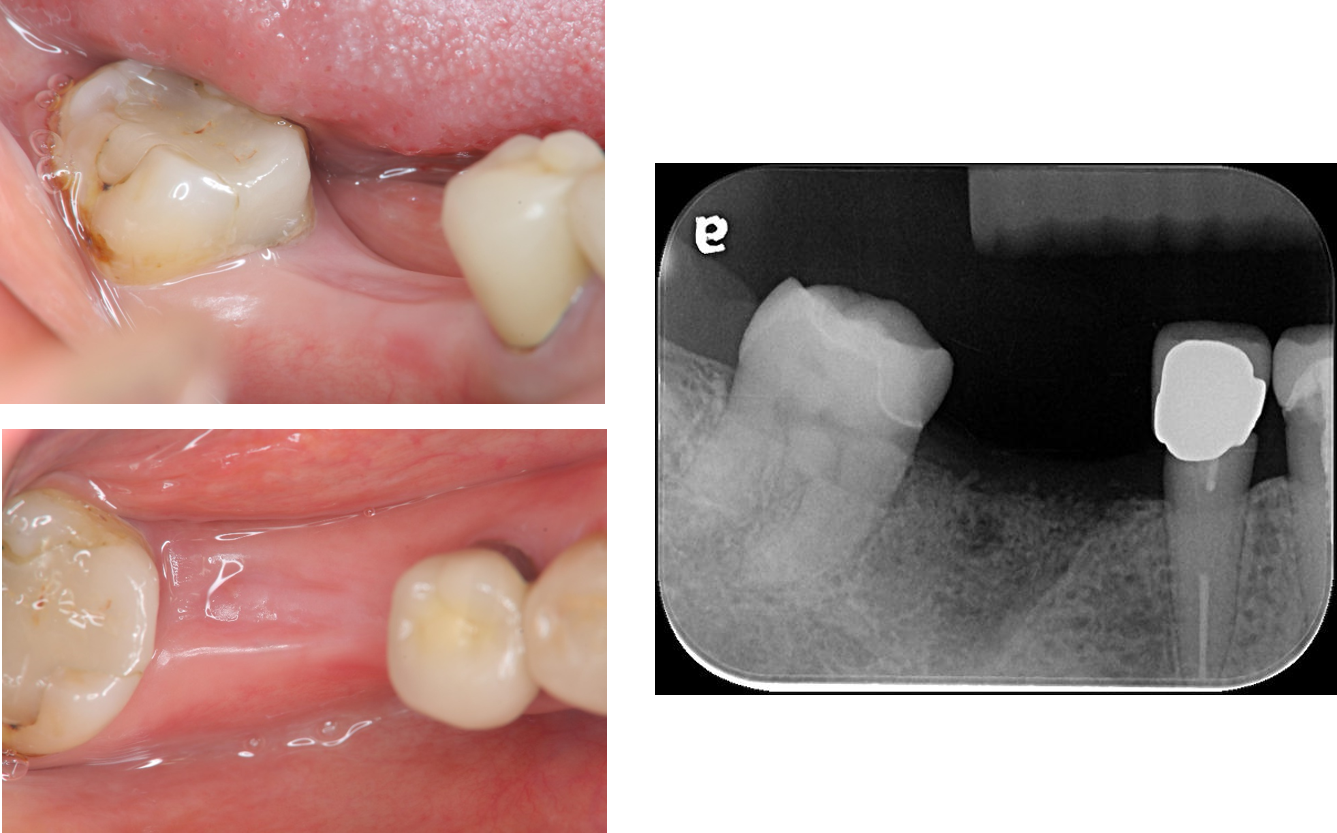

植牙時同時補皮